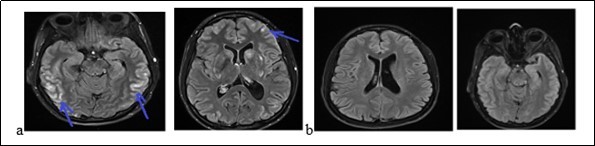

A 31-year-old pregnant woman was admitted to hospital because of headaches, vomiting and rotational dizziness on December 29, 2017. A series of headache followed by vomiting and dizziness began at 33 weeks of pregnancy (a month before her admission). We noticed that the blood pressure reached 150 / 90mmHg. She was treated with oral nicardipine for one month. The delivery took place without postpartum complications. She had been treated with bromocriptine for breast congestion. Three days after delivery, she had thunderclap posterior headache, nausea chills with asthenia without fever, polyuria and polydipsia. The manifestation of the headache was 9.5 / 10 on the Visual analogical Scale. In her medical history, she underwent a surgery of an ovarian cyst and a left temporal arachnoid cyst in 2007. She is an active smoker at 15 boxes-years. The neurological and other physical examinations were normal. The routine biological, metabolic, infectious and immunological check-up was normal. The MRI had displayed a subarachnoid hemorrhage associated with hypersignals on Flair sequences of bilateral hemispherical cortex, on the central gray nuclei and the cerebellar hemispheres. The Angiography had not shown any stenosis. The MRI (Figure 3) had displayed on diffusion sequences, two punctiform infarction of right putamen and caudate nuclei. The apparent diffusion coefficient was high for the other bi-frontal lesions. All these findings led us to conlude with RPE syndrome complicated by subarachnoid hemorrhage and cerebral ischemia. The patient had been treated with decreasing dose of nimodipine for three months. At 6 weeks of progress, the neurological examination was normal. The Brain MRI (Figure 3b) displayed a complete decrease of the flair hyper signals from the basal ganglia and the cortex. The outcome was good.

Figure 3.The brain MRI with flair sequences showing bi-temporal and frontal hyper signals (a) and a complete decrease of lesions after treatment (b).